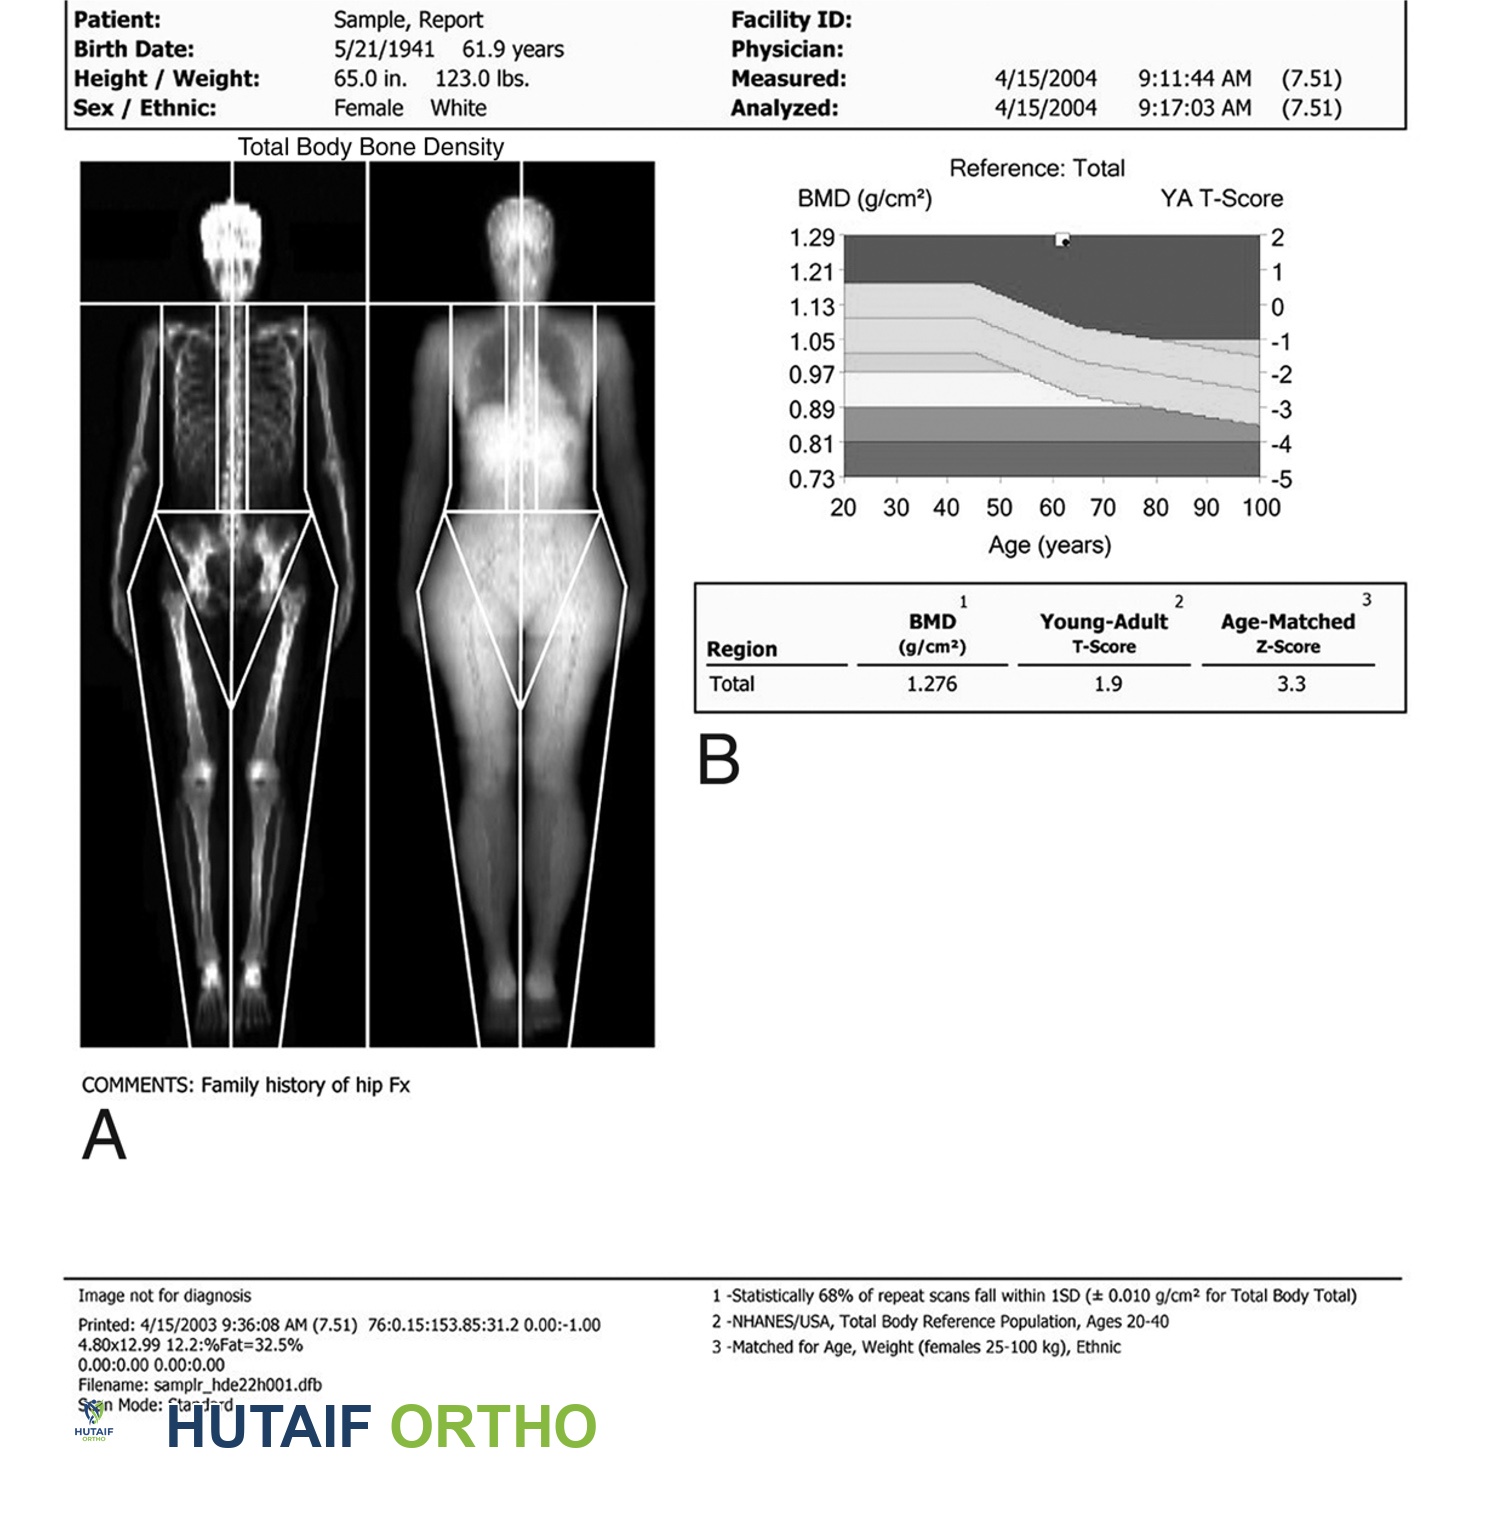

يوضح هذا المخطط الكتلة العظمية لدى النساء وعلاقتها بالعمر.

مُعاد إنتاجه من J Bernstein, ed: Musculoskeletal Medicine. Rosemont, IL, American Academy of Orthopaedic Surgeons, 2003.

إذا أصبحت دورتك الشهرية غير منتظمة، أو إذا ظهرت عليك علامات سن اليأس، مثل الهبات الساخنة، تحدثي مع طبيبك. قد ترغبين أيضًا في السؤال عن اختبار كثافة العظام. إنها تقنية آمنة وغير مؤلمة بالأشعة السينية تقارن كثافة عظامك الحالية بذروة الكتلة العظمية التي كان يجب أن يصل إليها شخص من نفس جنسك وعرقك في سن 20 إلى 25 عامًا. يؤكد الأستاذ الدكتور محمد هطيف على أهمية الكشف المبكر والتقييم الدقيق لتحديد أفضل مسار علاجي.

يُعد فحص امتصاص الأشعة السينية ثنائي الطاقة (DXA) "المعيار الذهبي" لاختبار كثافة المعادن في العظام.

مُعاد إنتاجه بإذن من JF Sarwark, ed: Essentials of Musculoskeletal Care, ed 4. Rosemont, IL, American Academy of Orthopaedic Surgeons, 2010